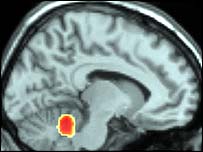

Đây là hình chụp não khi phụ nữ thật sự đạt đỉnh: não gần như không hoạt động

Lý do là vì trong cơn cực khoái thật sự, vùng vỏ não, điều khiển phần ý thức của não, đóng lại hoàn toàn.

Máy scan cho thấy trong lúc hoạt động tình dục, những phần trong não phụ nữ có tác dụng kiểm soát nỗi sợ, lo lắng và tình cảm bắt đầu thư giãn và giảm hoạt động. Nó đạt tới đỉnh khi cực khoái, khi mà các trung tâm tình cảm trong não phụ nữ đóng hẳn lại.

"Điều chính mà chúng tôi thấy ở người phụ nữ là sự ngưng kích hoạt ở não, rất rõ rệt và không thể tin được. Đây là kết quả chính của nghiên cứu. Ta thấy có sự ngưng kích hoạt ở nhiều phần trong não, đặc biệt là ở khu vực kiểm soát tình cảm và sợ hãi."